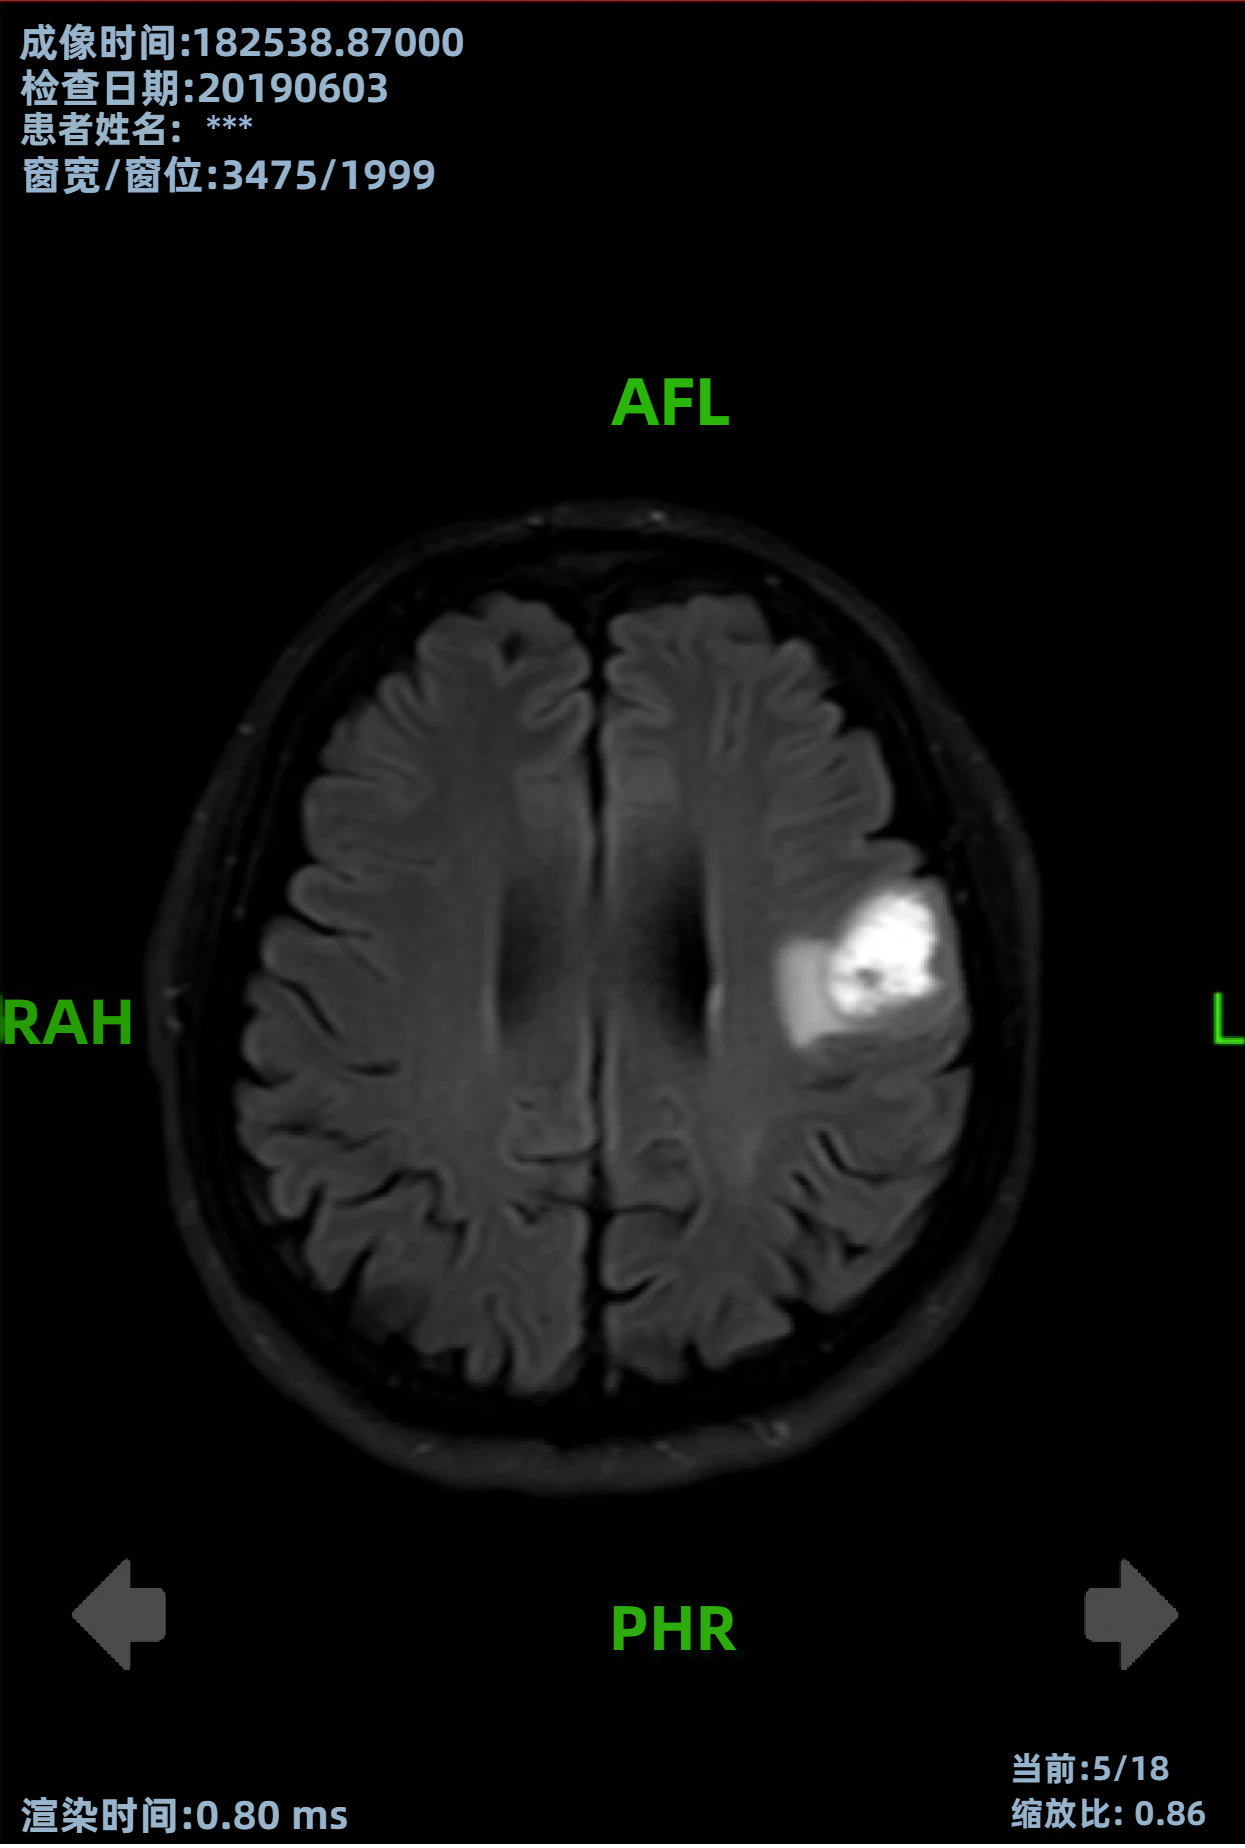

病史摘要:30岁男性患者,有大量饮酒史,无吸烟及非法药物使用史,否认胃肠道恶性肿瘤等家族史。因精神状态改变被送至急诊科。 诊疗过程:初始检查发现中度转氨酶升高,尿毒物筛查大麻素阳性,多种病毒血清学阴性。影像学检查发现孤立性左肾、输尿管结石伴急性肾损伤及腹腔肿块等。肿瘤标志物大多正常,LDH升高等。CT引导下活检,病理及免疫组化有相应表现。初步诊断为起源于胰腺的异位肝细胞癌伴广泛转移,先接受